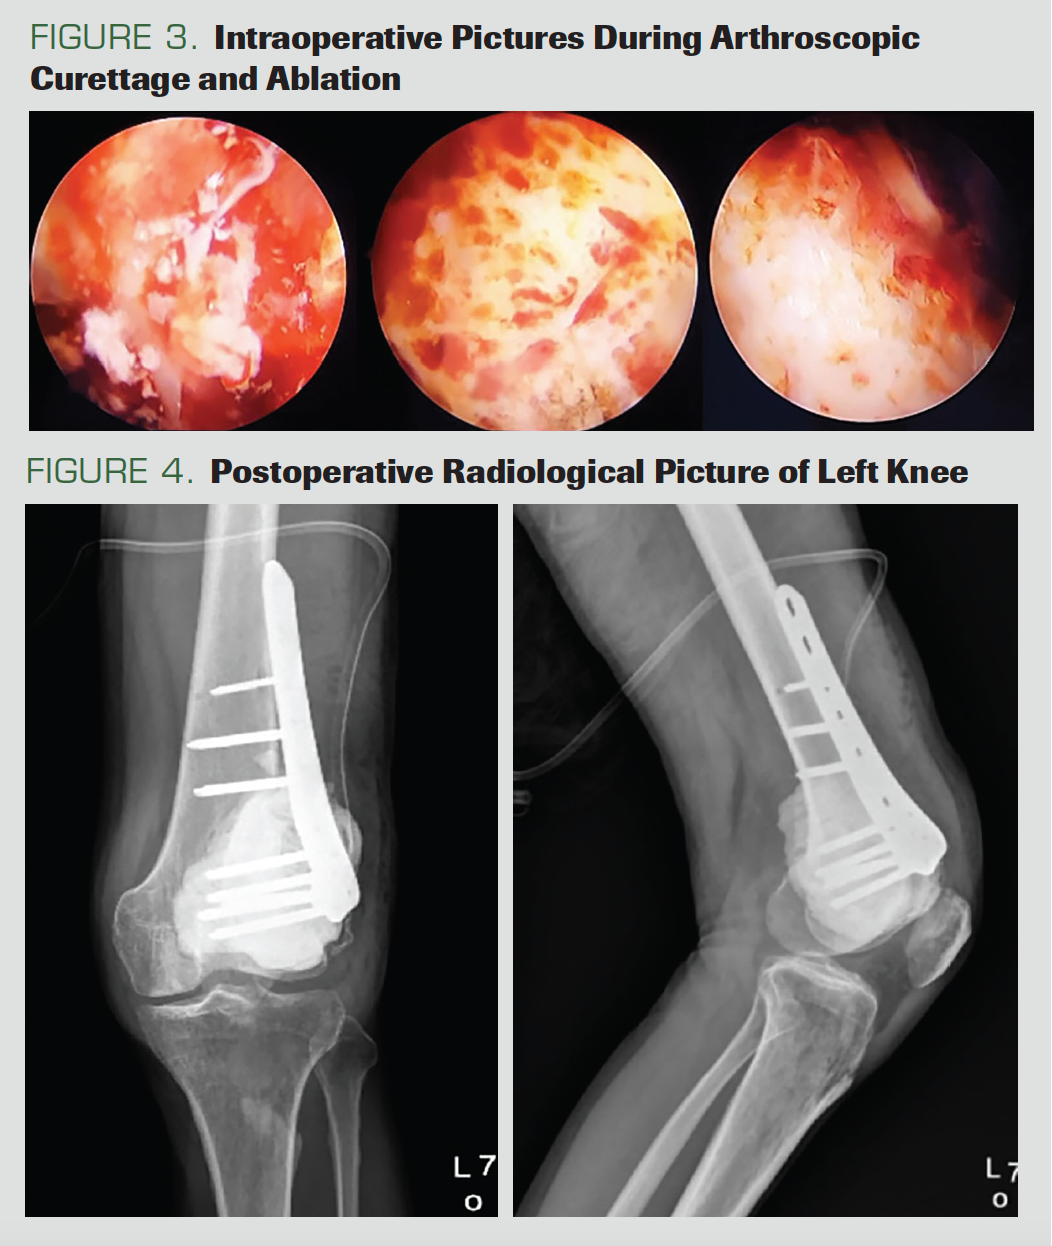

FIGURES 3 & 4.

During the surgery, the patient was positioned supine, with the knee in 90° flexion. An incision was made for lateral portal insertion, at the soft spot above the joint line 2 cm lateral to the patellar tendon. The hematoma was drained, and an anteromedial portal was established with an outside-in technique. The joint was then irrigated with copious amounts of saline solution. A guide wire was passed from the lateral femoral condyle using a 6.5-mm drill bit. The presence of a mass on the lateral condyle of the femur was confirmed, and a sample taken for frozen section examination demonstrated a histological result in accordance with GCTB. A lateral longitudinal incision was made on the distal femur, extending up to expose the tumor. The fascia was incised to expose the lateral femoral condyle. Curettage and ablation were performed arthroscopically. A cortical window measuring 2 × 2 cm was made with an intact periosteal hinge. A 30° arthroscope with a light source was introduced through the cortical window. After the introduction of the scope, the light source cable was rotated to provide a 360° visualization of the tumor cavity. The surrounding structure of the cortical window was covered with a sterile mop to avoid spillage of the tumor cells or of irrigation fluid in the surrounding tissue. A small curette, 4.5-mm shaver tip, and high-speed burr were interchangeably used to curette the GCTB cavity. The end point of curettage was the visualization of the normal cortical bone through the arthroscope. During the curettage, copious amounts of normal saline were used for irrigation of the cavity. After curettage, the cavity was filled with polymethyl methacrylate cement. A distal femoral locking plate with 5 holes and 8 screws was then installed with the minimally invasive plate osteosynthesis (MIPO) technique. After hemostasis was achieved, the incision was closed in layers over a drain. The operation procedure and radiograph after the procedure are shown in Figure 3 and Figure 4.

Knee ROM exercises were started immediately postoperatively, as tolerated. The patient was advised to walk with 2 crutches and to not bear weight for 4 weeks, before gradually increasing weight according to his pain tolerance. He was asked to return for outpatient follow-up every month for the initial 6 months. After 1 year of follow-up, the patient has full ROM and has demonstrated no sign of recurrence on serial radiography and a satisfactory functional outcome; he has returned to his occupational and daily activities (Figure 5 and Figure 6).